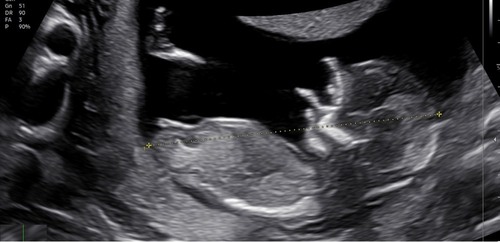

Je hebt een speciaal topic hier voor. Als je zoekt op nub topic dan kom je er een paar tegen daar kan je je echo plaatsen. Dit topic zal zometeen gesloten worden, ik persoonlijk kan hier niks van maken ik zou even een andere foto zoeken vanaf de zijkant.

Als ik moet gokken dan denk ik een jongen aan het uitstekende gedeelte te zien maar ik ben geen prof 🙃.

Meisje

Idd even in het speciale topic hiervoor plaatsen. Maar ik zou zeggen meisje :) nub loopt naar mijn idee evenwijdig aan de ruggegraat